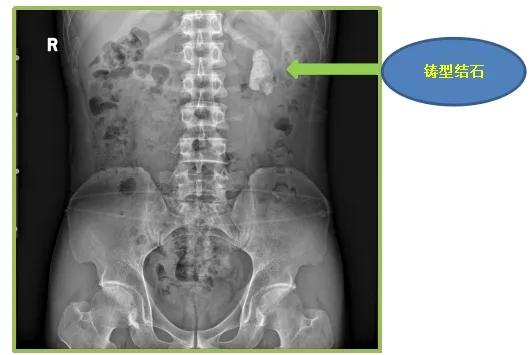

日前,我接诊了一位因腰痛前来就诊的刘先生,从泌尿系B超和腹部CT结果上看,刘先生的左肾有一大块铸型结石,大小约5.1cm×2.8cm的结石充满了左肾。